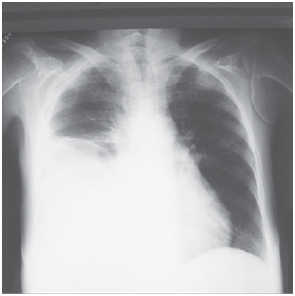

Mulher, 21 anos, apresenta febre, mialgia, cefaleia, dor retro-orbitária e náuseas há 6 dias. Exame físico: bom estado geral, corada e desidratada +/4+; bulhas rítmicas e normofonéticas, sem sopros; FC: 102 bpm; PA: 110 x 60 mmHg; murmúrio vesicular reduzido no terço inferior do hemitórax direito; FR = 26 ipm; abdome: ruídos presentes; dor moderada à palpação profunda em mesogástrio, sem visceromegalias; presença de edema +/4+, depressível em membros inferiores; presença de petéquias em ambas as pernas. Exames complementares: Hb = 13,9 g/dL; Ht = 42%; leucócitos = 2 900/mm3 (segmentados: 34%; linfócitos: 61%); plaquetas: 18 000/mm3; AST = 122 (VR < 32 U/L); ALT = 62 (VR < 31 U/L); pesquisa do antígeno NS1 para dengue negativo. Ultrassonografia de abdome: ascite de moderado volume. A radiografia de tórax encontra-se ilustrada a seguir.

Assinale a alternativa que apresenta a conduta mais adequada.